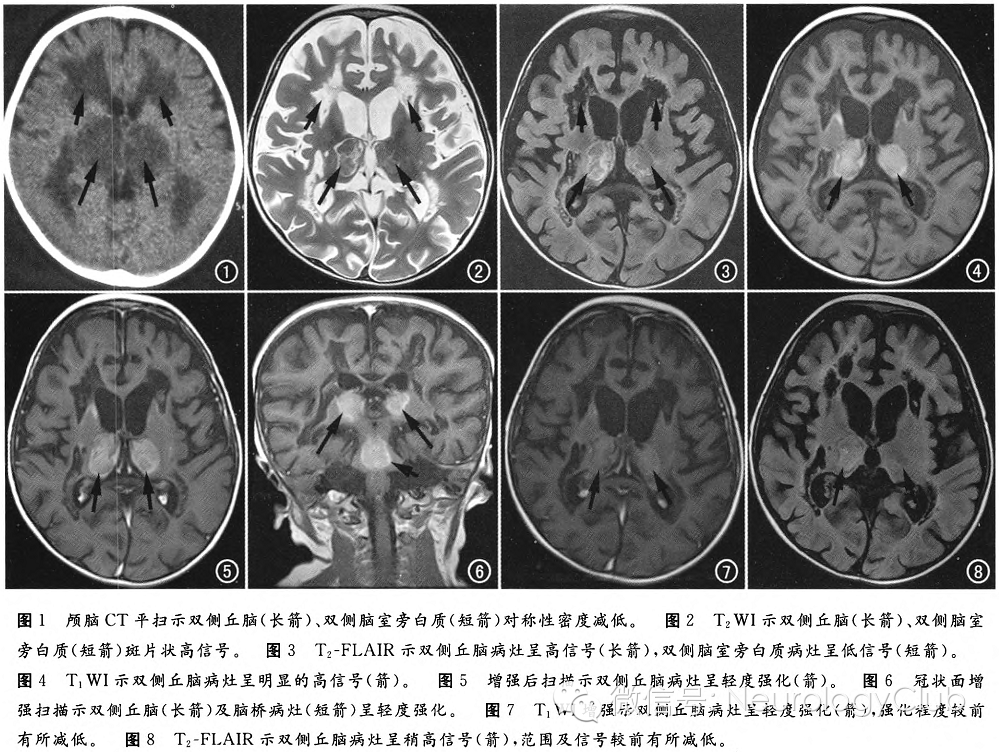

头颅CT提示:双侧丘脑、大脑脚、中脑及桥脑可见肿胀、对称性低密度病灶,双侧脑室旁白质密度对称性减低(图1)。头颅MRI显示:双侧放射冠、半卵圆中心、双侧丘脑、中脑、大脑脚、脑桥可见多发类圆形斑片状异常信号,大小不等,形态不规则。T1WI呈高或低信号,T2WI及T2-FLAIR呈周边环状高信号,增强扫描示双侧放射冠及双侧丘脑、脑桥病灶轻度强化。双侧侧脑室稍扩张,双侧额颞叶脑池、脑裂增宽(图2-6)。治疗1个月后复查MRI(图7-8),双侧丘脑病灶范围及强化程度较前有所减轻。

ANE最突出的影像学表现是对称性的累及双侧丘脑,而且T1WI常呈高信号。其他病变部位包括脑室旁深部脑白质、脑干、内囊、豆状核及小脑等。ANE的CT图像表现为上述病变部位对称性的密度减低。MRI表现为上述病变区对称性异常信号,T2WI呈高信号,丘脑病变T1WI常呈高信号,而其他部位病变T1WI一般呈低信号,增强后一般无强化或只有轻度强化。本例患儿病变累及双侧丘脑、大脑脚、中脑及桥脑,双侧丘脑病变T1WI呈明显高信号,这与相关文献报道相一致。ANE的病理学表现为病变区水肿、点状出血和坏死,病变内没有炎细胞是其特点,是病理上与急性播散性脑炎和急性出血性脑炎相鉴别的要点。组织学上ANE患者的双侧丘脑、脑干、小脑齿状核及深部脑白质表现为严重的水肿,这些病变部位的水肿最终导致神经细胞和胶质细胞坏死。ANE脑白质病变区的水肿为不含红细胞的血浆样物质大量渗出,而丘脑等灰质结构的病变,除水肿外,还伴有血管周围的多发出血,这就是ANE患者丘脑等灰质结构出现T1WI高信号的原因